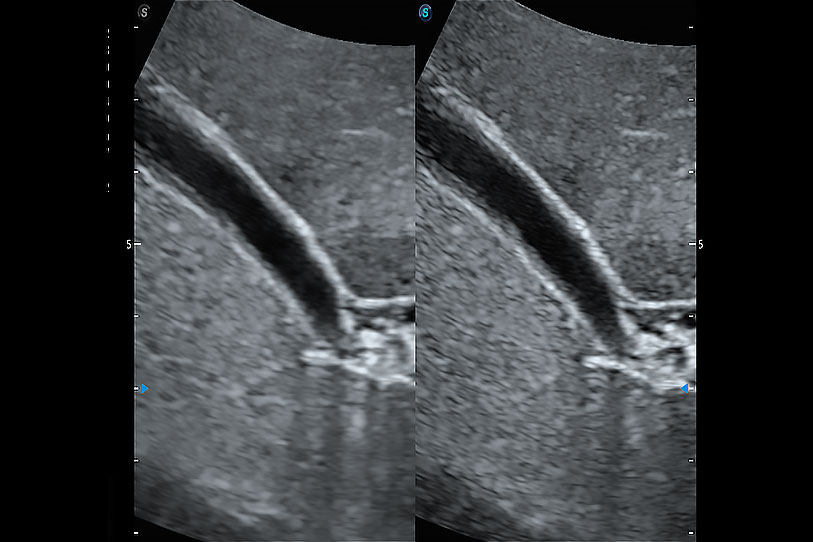

通過(guò)色彩血流和實(shí)時(shí)寬景相結(jié)合,可觀察到完整的靜脈或動(dòng)脈的血流,方便醫(yī)生檢查。實(shí)時(shí)掃查過(guò)程中,如有任何操作失誤也可以很容易地進(jìn)行回掃擦除,而不會(huì)中斷掃查。